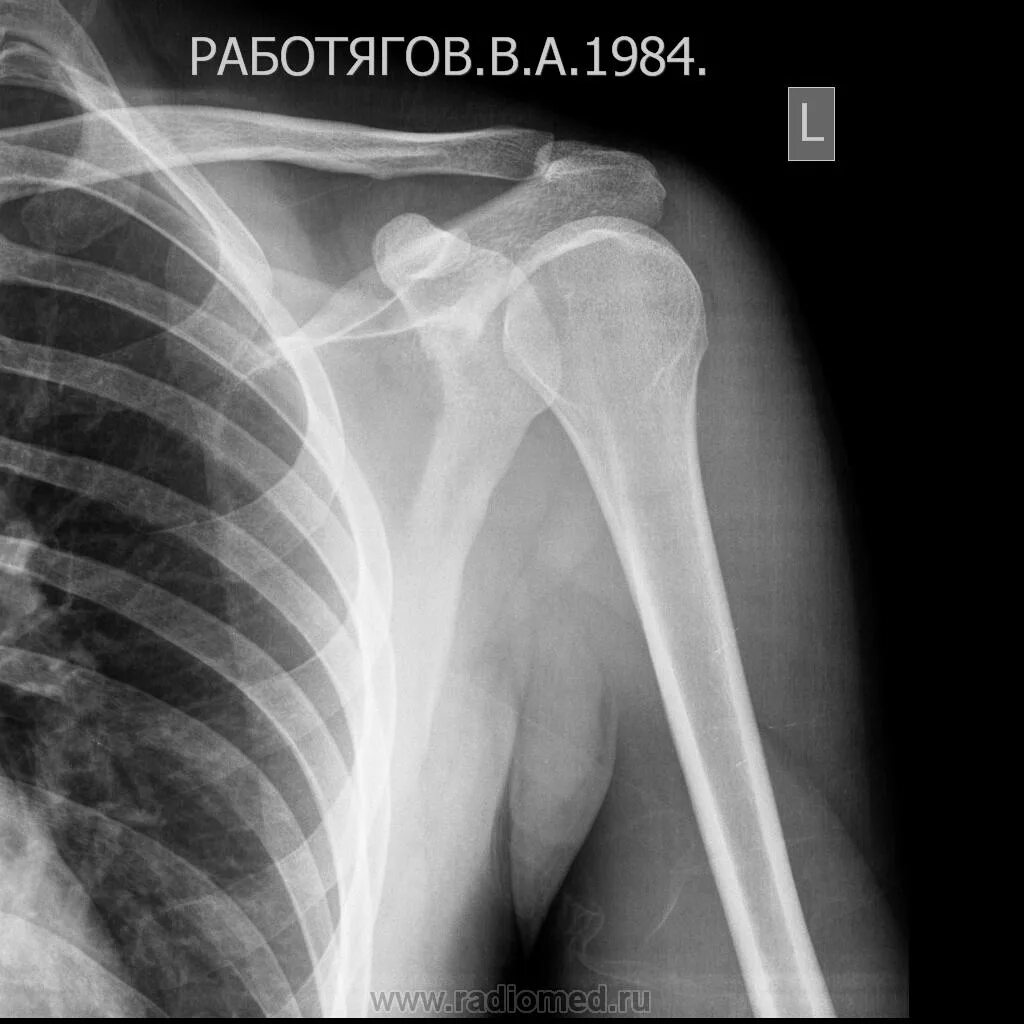

Деформирующий акромиально ключичного сочленения